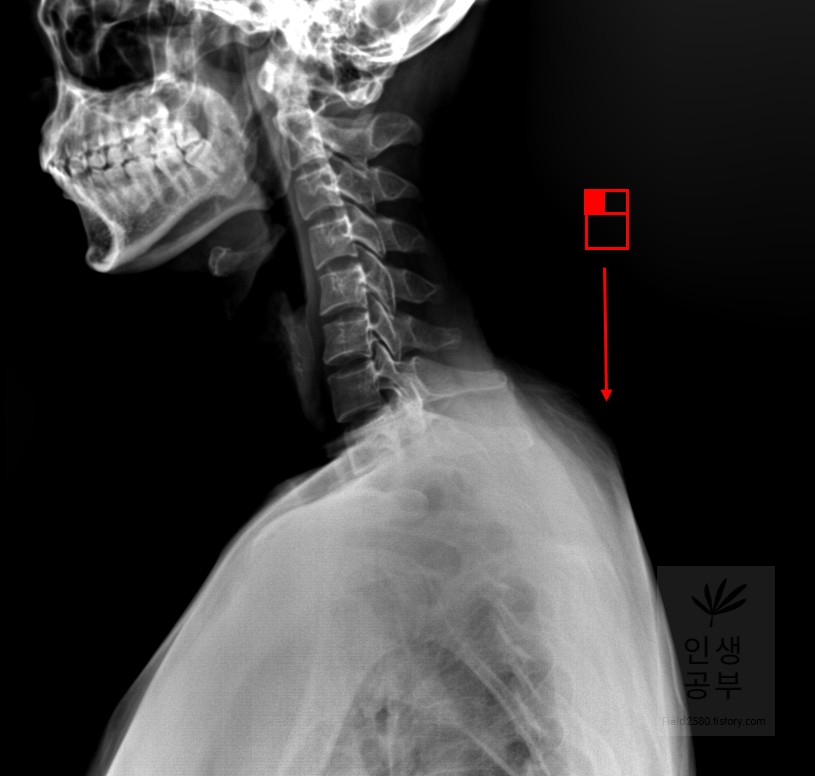

마우스 오른쪽 버튼을 누르고 위쪽 방향으로 드래그 해주면 화면이 밝아집니다.

마우스 오른쪽 버튼을 누르고 아래쪽 방향으로 드래그 해주면 화면이 어두워집니다. 두 버튼 모두 엑스레이가 잘 보이지 않을 때 적절하게 밝기를 조절하여 사용하시면 됩니다.

돋보기 화면이 있는데 확대 축소하는 방법에 대해서 알아보겠습니다. 화면 전체를 확대하거나 축소할 때는 도구모음에 돋보기 화면에 ±가 있는 버튼을 눌러줍니다. 빨간색 네모상자 안에 있는 버튼이 확대하거나 축소할 때 사용하는 버튼입니다. 부분적인 부분만 확대해서 보고 싶을 때는 매직 글래스라는 메뉴를 이용해서 부분적인 확대를 할 수 있습니다. 먼저 화면 전체를 확대하거나 축소할 대 쓰는 도구모음 버튼을 어떻게 사용하는지에 대해서 알아보겠습니다.

버튼을 누르고 기본 엑스레이 화면에 마우스 왼쪽 버튼을 클릭해줍니다.

마우스 왼쪽 버튼을 누른 상태에서 위쪽으로 올려주면 화면이 확대됩니다. 확대된 상태에서는 돋보기 버튼이 눌러진 채로는 이동할 수 없습니다.

확대된 화면에서 화면 이동을 위해서는 손가락모양이 있는 버튼을 따로 클릭해 주어야 합니다. 빨간 네모칸 안에 있는 손가락 모양으로 된 버튼을 눌러줍니다. 이 손가락 모양 버튼은 화면이 확대되거나 축소되었을 때, 혹은 다른 버튼을 이용해서 화면의 변화가 생겼을 때 움직이도록 만들어줄 수 있게 만든 버튼입니다.

확대된 화면에 왼쪽 마우스를 누른 후, 확대해서 보고싶은 화면으로 이동시켜주면 화면전체를 이동할 수 있습니다.

다음으로 화면 전체를 축소시키는 방법에 대해서 알아보겠습니다. 확대했을 때와 마찬가지로 도구모음에 돋보기 화면에 ±가 있는 버튼을 눌러줍니다.

X-ray 화면에 왼쪽 마우스를 클릭한 후 아래로 드래그해서 내려주면 다시 축소됩니다. 확대 축소 버튼과 손가락 모양을 이용해서 본인이 보고 싶거나 환자가 더 자세하고 크게 보고 싶어하는 부분을 이 버튼을 이용해서 화면 크기를 조절해서 볼 수 있습니다. 저 같은 경우에는 환자분들이 연령대가 있어서 X-ray 화면이 잘 안보이시는 분에게 크게 보여줄 때 사용합니다. 특히 뼈의 퇴행성질환이나 만곡도를 보여줄 때 많이 사용합니다.

돋보기 화면에 ±가 있는 버튼을 이용해서 화면 전체의 크기를 조절할 수 있는 반면에 부분적인 부분만 확대할 수 있는 방법이 있습니다. 바로 매직 글래스메뉴를 이용해서 부분적인 확대 버튼을 이용하실 수 있습니다. 또한 부분적인 확대 화면 안에서도 추가적인 확대와 축소를 이용할 수 있습니다.

X-ray화면 창에서 마우스 오른쪽 버튼을 클릭해 줍니다. 그 후에 매직 글래스라고 적힌 항목을 선택해줍니다.

부분적으로 확대해서 보고 싶은 X-ray화면에 마우스 왼쪽을 클릭해서 확대해줍니다. 부분적으로 네모칸이 생기면서 선택한 부분을 조금더 크게 보여주는 창이 생깁니다.